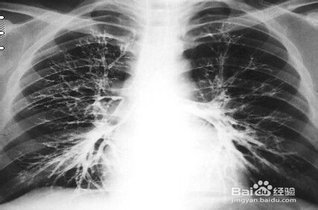

学会看胸片是临床医生必备的技能之一,首先,看胸壁的X线表现,观察胸壁软组织有大的肿块,有皮下积液、积气,同时观察肋骨的连续性是否有中断,这是肋骨骨折的X线征象...73227人收听

在临床上胸部X光片检查是常用的一种检查方法,它是利用X线产生图像,从而观察胸部的病变。胸片的观察需要按一定的顺序,一般可以按照从上往下的顺序,观察双肺上叶...1人收听

胸片就是普通x线胸部平片,一般都是拍胸部正位片。胸部正位片主要显示的是两侧的肺野,心影轮廓大小,胸椎,以及肋骨。作为影像科普通的检查,方便、快捷,为临床科室解决了许多常见的问题。比如...